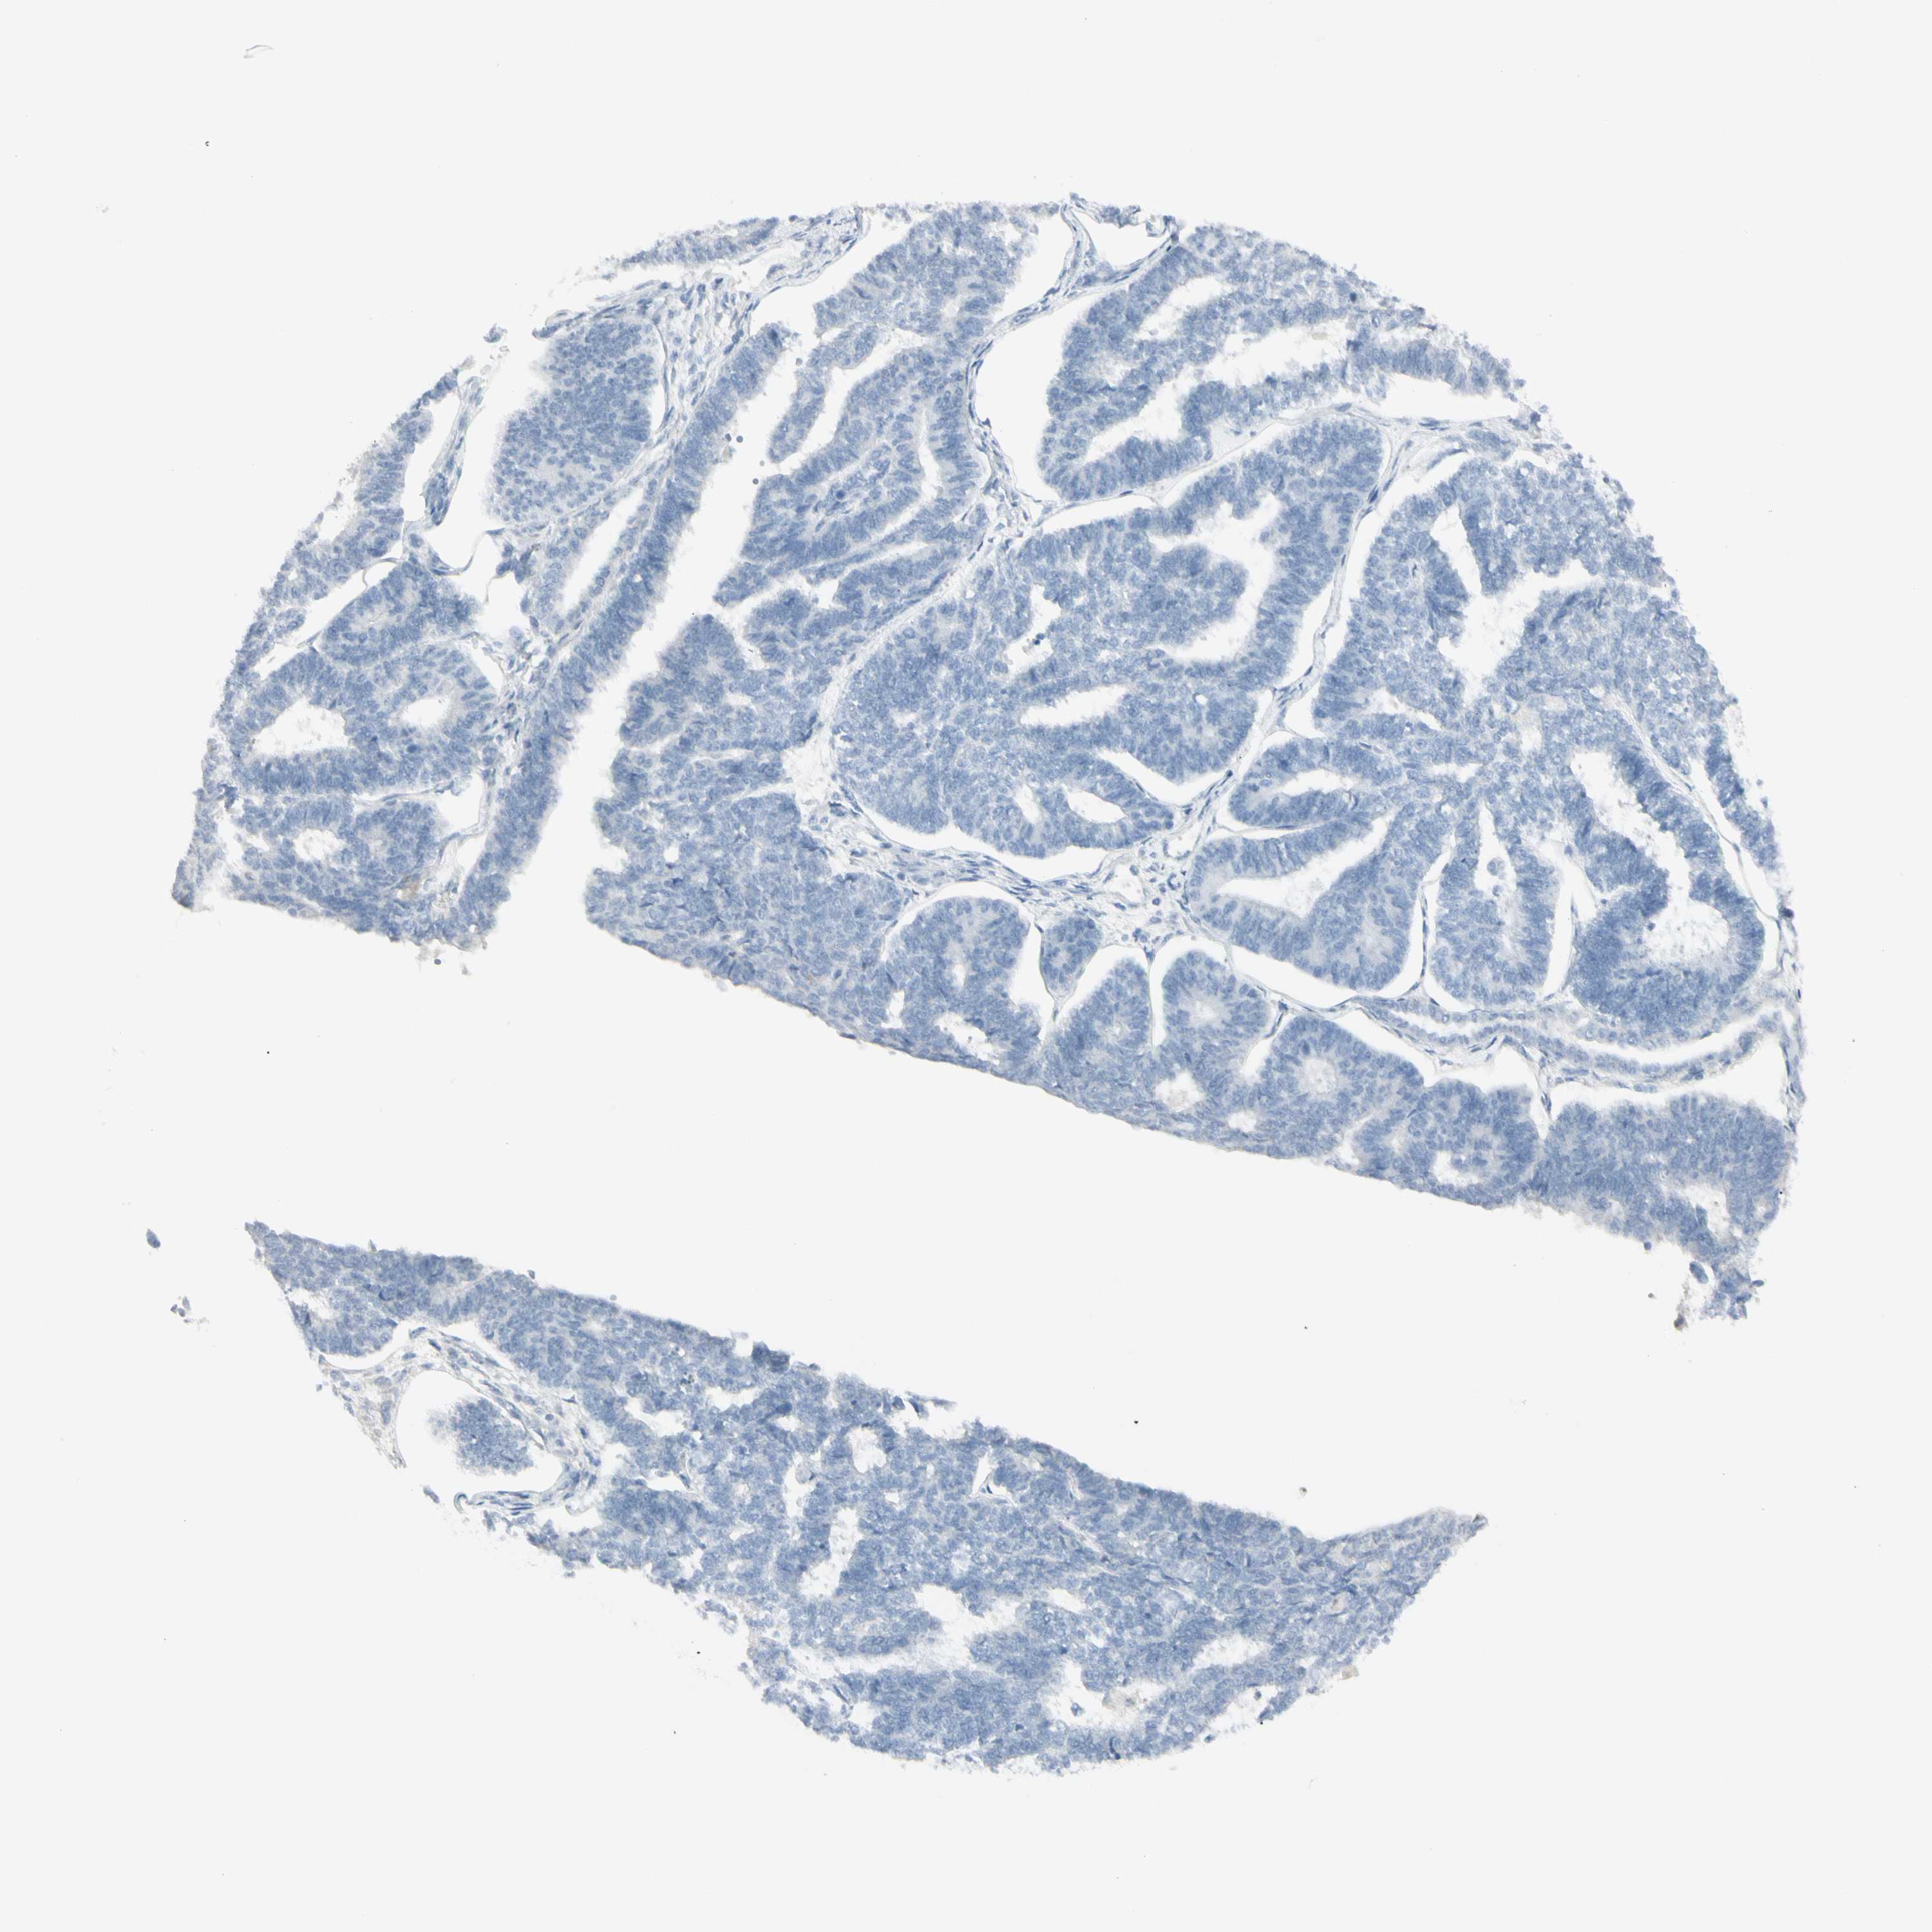

ENDOMETRIAL CANCER - Protein expressioni

A mouse-over function shows sample information and annotation data. Click on an image to view it in a full screen mode. Samples can be filtered based on level of antibody staining by selecting one or several of the following categories: high, medium, low and not detected. The assay and annotation is described here.

Note that samples used for immunohistochemistry by the Human Protein Atlas do not correspond to samples in the TCGA dataset.

Antibody stainingi

Antibody staining in the annotated cell types in the current human tissue is reported as not detected, low, medium, or high, based on conventional immunohistochemistry profiling in selected tissues. This score is based on the combination of the staining intensity and fraction of stained cells.

Each image is clickable and will lead to virtual microscopy that enables deeper exploration of all samples and also displays staining intensity scores, fraction scores and subcellular localization as well as patient and tissue information for each sample.

Antibody HPA009177

Antibody CAB002661

Staining

High

Medium

Low

Not detected

Intensity

Strong

Moderate

Weak

Negative

Quantity

>75%

75%-25%

<25%

None

Location

Nuclear

Cytoplasmic/membranous

Cytoplasmic/membranous,nuclear

Adenocarcinoma, NOS

Neoplasm, malignant, NOS